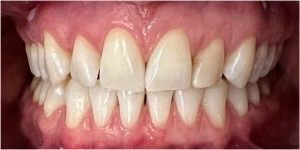

Następnie została wykonana wizualizacja nowego uśmiechu, idealnie dopasowana do twarzy Pacjentki. Po jej akceptacji, przygotowaliśmy komplet koron i licówek pełnoceramicznych na górne i dolne zęby.

Całe leczenie trwało zaledwie 3 miesiące!

Dzięki współpracy lek. stom. Michała Badowskiego i techn. dent. Joanny Gancarz z laboratorium Dentalscan Pacjentka zachwyca pięknym uśmiechem!